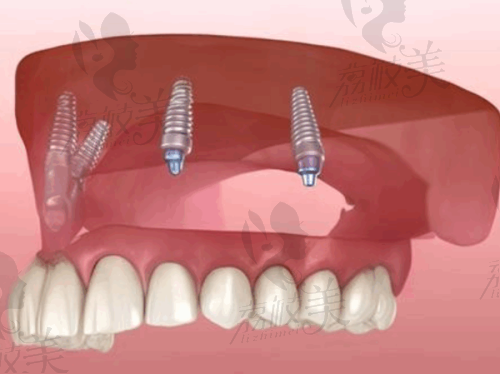

种植牙国产种植牙4200元/颗起牙齿缺失患者能正常享受美食,提升生活质量

全口种植牙8万元起 - 35万元左右全口牙齿缺失者修复正常咀嚼和说话功能

穿颧穿翼种植22,000元/颗骨缺损患者解决骨量不足的种植难题